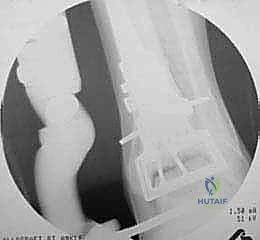

* Fluoroscopic Confirmation: Before making any cuts, confirm the placement and size of the cutting block with intraoperative fluoroscopy in AP, lateral, and mortise views. This is a non-negotiable step to ensure accuracy and prevent malalignment.

2. Tibial Plafond Resection:

* Using a blunt reciprocating saw with the blade guided by the cutting block, resect the distal tibial plafond. Our target depth is approximately 7 to 10 mm.

* Once the tibial cut is complete, reposition the cutting block for the talus. Pin it securely.

* Again, using the blunt reciprocating saw guided by the cutting block, resect the talar dome to a depth of approximately 7 to 10 mm. Ensure the cut is perpendicular to the mechanical axis of the tibia.

* Goal: The goal is to create flat, parallel, and stable recipient beds for the allografts.

- Fluoroscopic Confirmation of Apposition and Anatomy: